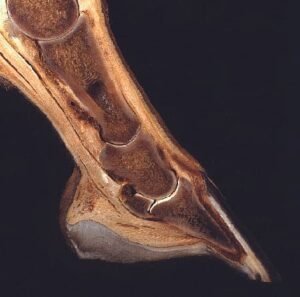

La laminitis equina, también conocida comúnmente como infosura, es una de las enfermedades más dolorosas, graves y potencialmente devastadoras que pueden afectar a los caballos. Consiste en la inflamación y a su vez una disminución del flujo sanguíneo causando el debilitamiento de las láminas, que son los tejidos blandos que actúan conectando el hueso tejuelo (tercera falange) con la pared interna del casco.